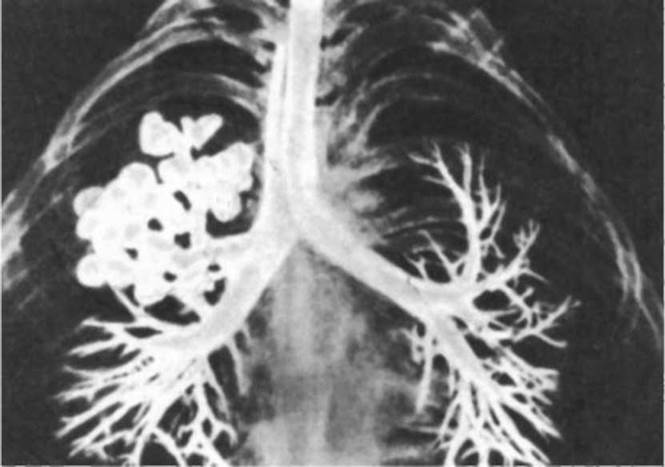

В эмбриогенезе человека отражается первоначальное единство пищеварительной и дыхательной систем. На этом основано формирование большой группы врожденных пороков развития пищевода и трахеи типа эзофаготрахеальных свищей (рис. 14.27). Нарушением альвеолярной дифференцировки легочной ткани могут быть объяснены дизонтогенетические бронхолегочные кисты - округлые полости в легких, отграниченные от окружающих тканей примитивно построенной стенкой недифференцированного бронха, а также кистозная гипоплазия (недоразвитие) легких (рис. 14.28). При этой патологии недоразвитыми оказываются целые доли легкого, которые представляют собой многочисленные полости, связанные с крупными бронхами и имеющие малую площадь поверхности. Газообмен в таких участках легких резко ослаблен. Широко известны также гипоплазии диафрагмы от небольших дефектов в ее куполе до полной аплазии. Последняя аномалия несовместима с жизнью и встречается обычно вместе с другими множественными пороками развития.

Рис. 14.28. Кистозная гипоплазия правого легкого. Контрастная рентгенограмма